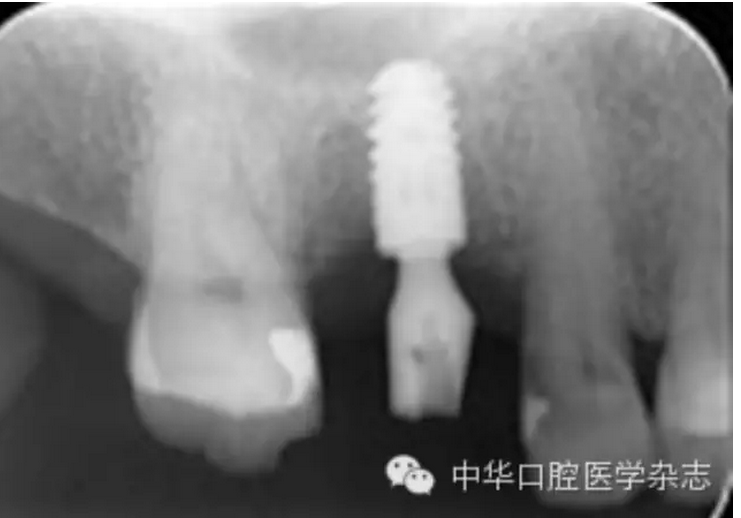

平臺(tái)轉(zhuǎn)換種植修復(fù)基臺(tái)折斷六例原因分析

【摘要】目的 分析平臺(tái)轉(zhuǎn)換種植修復(fù)基臺(tái)折斷原因,探討處理辦法及預(yù)防策略。方法 2001年1月至2014年12月植入的平臺(tái)轉(zhuǎn)換種植體2 487枚中,2009年3月至2014年2月發(fā)生平臺(tái)轉(zhuǎn)換種植修復(fù)基臺(tái)折斷6例,男性5例、女性1例,平均年齡63歲(55~78歲),均使用Ankylos®種植系統(tǒng),6例均為修復(fù)完成2~8年后發(fā)生修復(fù)基臺(tái)折斷。分析修復(fù)基臺(tái)折斷與力及其連接方式等因素的關(guān)系。結(jié)果 基臺(tái)折斷率為0.24%(6/2 487)。6例折斷基臺(tái)均發(fā)生在磨牙區(qū)、牙冠面均為貴金屬。6例折斷基臺(tái)均無(wú)法完整取出,最終取出種植體后重新種植修復(fù)。結(jié)論 平臺(tái)轉(zhuǎn)換種植修復(fù)基臺(tái)折斷后取出困難,應(yīng)注重預(yù)防此嚴(yán)重并發(fā)癥。磨牙區(qū)種植修復(fù)應(yīng)謹(jǐn)慎使用平臺(tái)轉(zhuǎn)換種植系統(tǒng);通過(guò)增加種植體數(shù)量、采取烤瓷聯(lián)冠修復(fù)可能降低基臺(tái)折斷風(fēng)險(xiǎn)。使用小直徑、短種植體可減少取出種植體時(shí)的創(chuàng)傷,有利于再次種植。